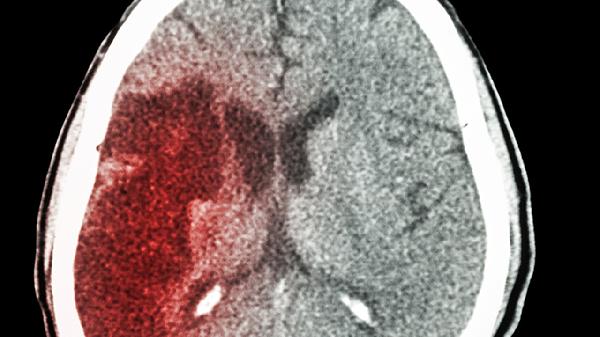

脑出血恢复健康可通过控制血压、康复训练、营养支持、心理疏导、定期复查等方式治疗。脑出血通常由高血压、脑血管畸形、外伤、凝血功能障碍、动脉瘤破裂等原因引起。

脑出血患者需定期进行头颅CT或MRI检查,评估出血吸收情况和脑组织恢复状态。同时需监测血压、血糖、血脂等指标,预防再次出血。出现头痛、呕吐、意识障碍等症状时需立即就医。长期随访可及时发现并发症,调整治疗方案。